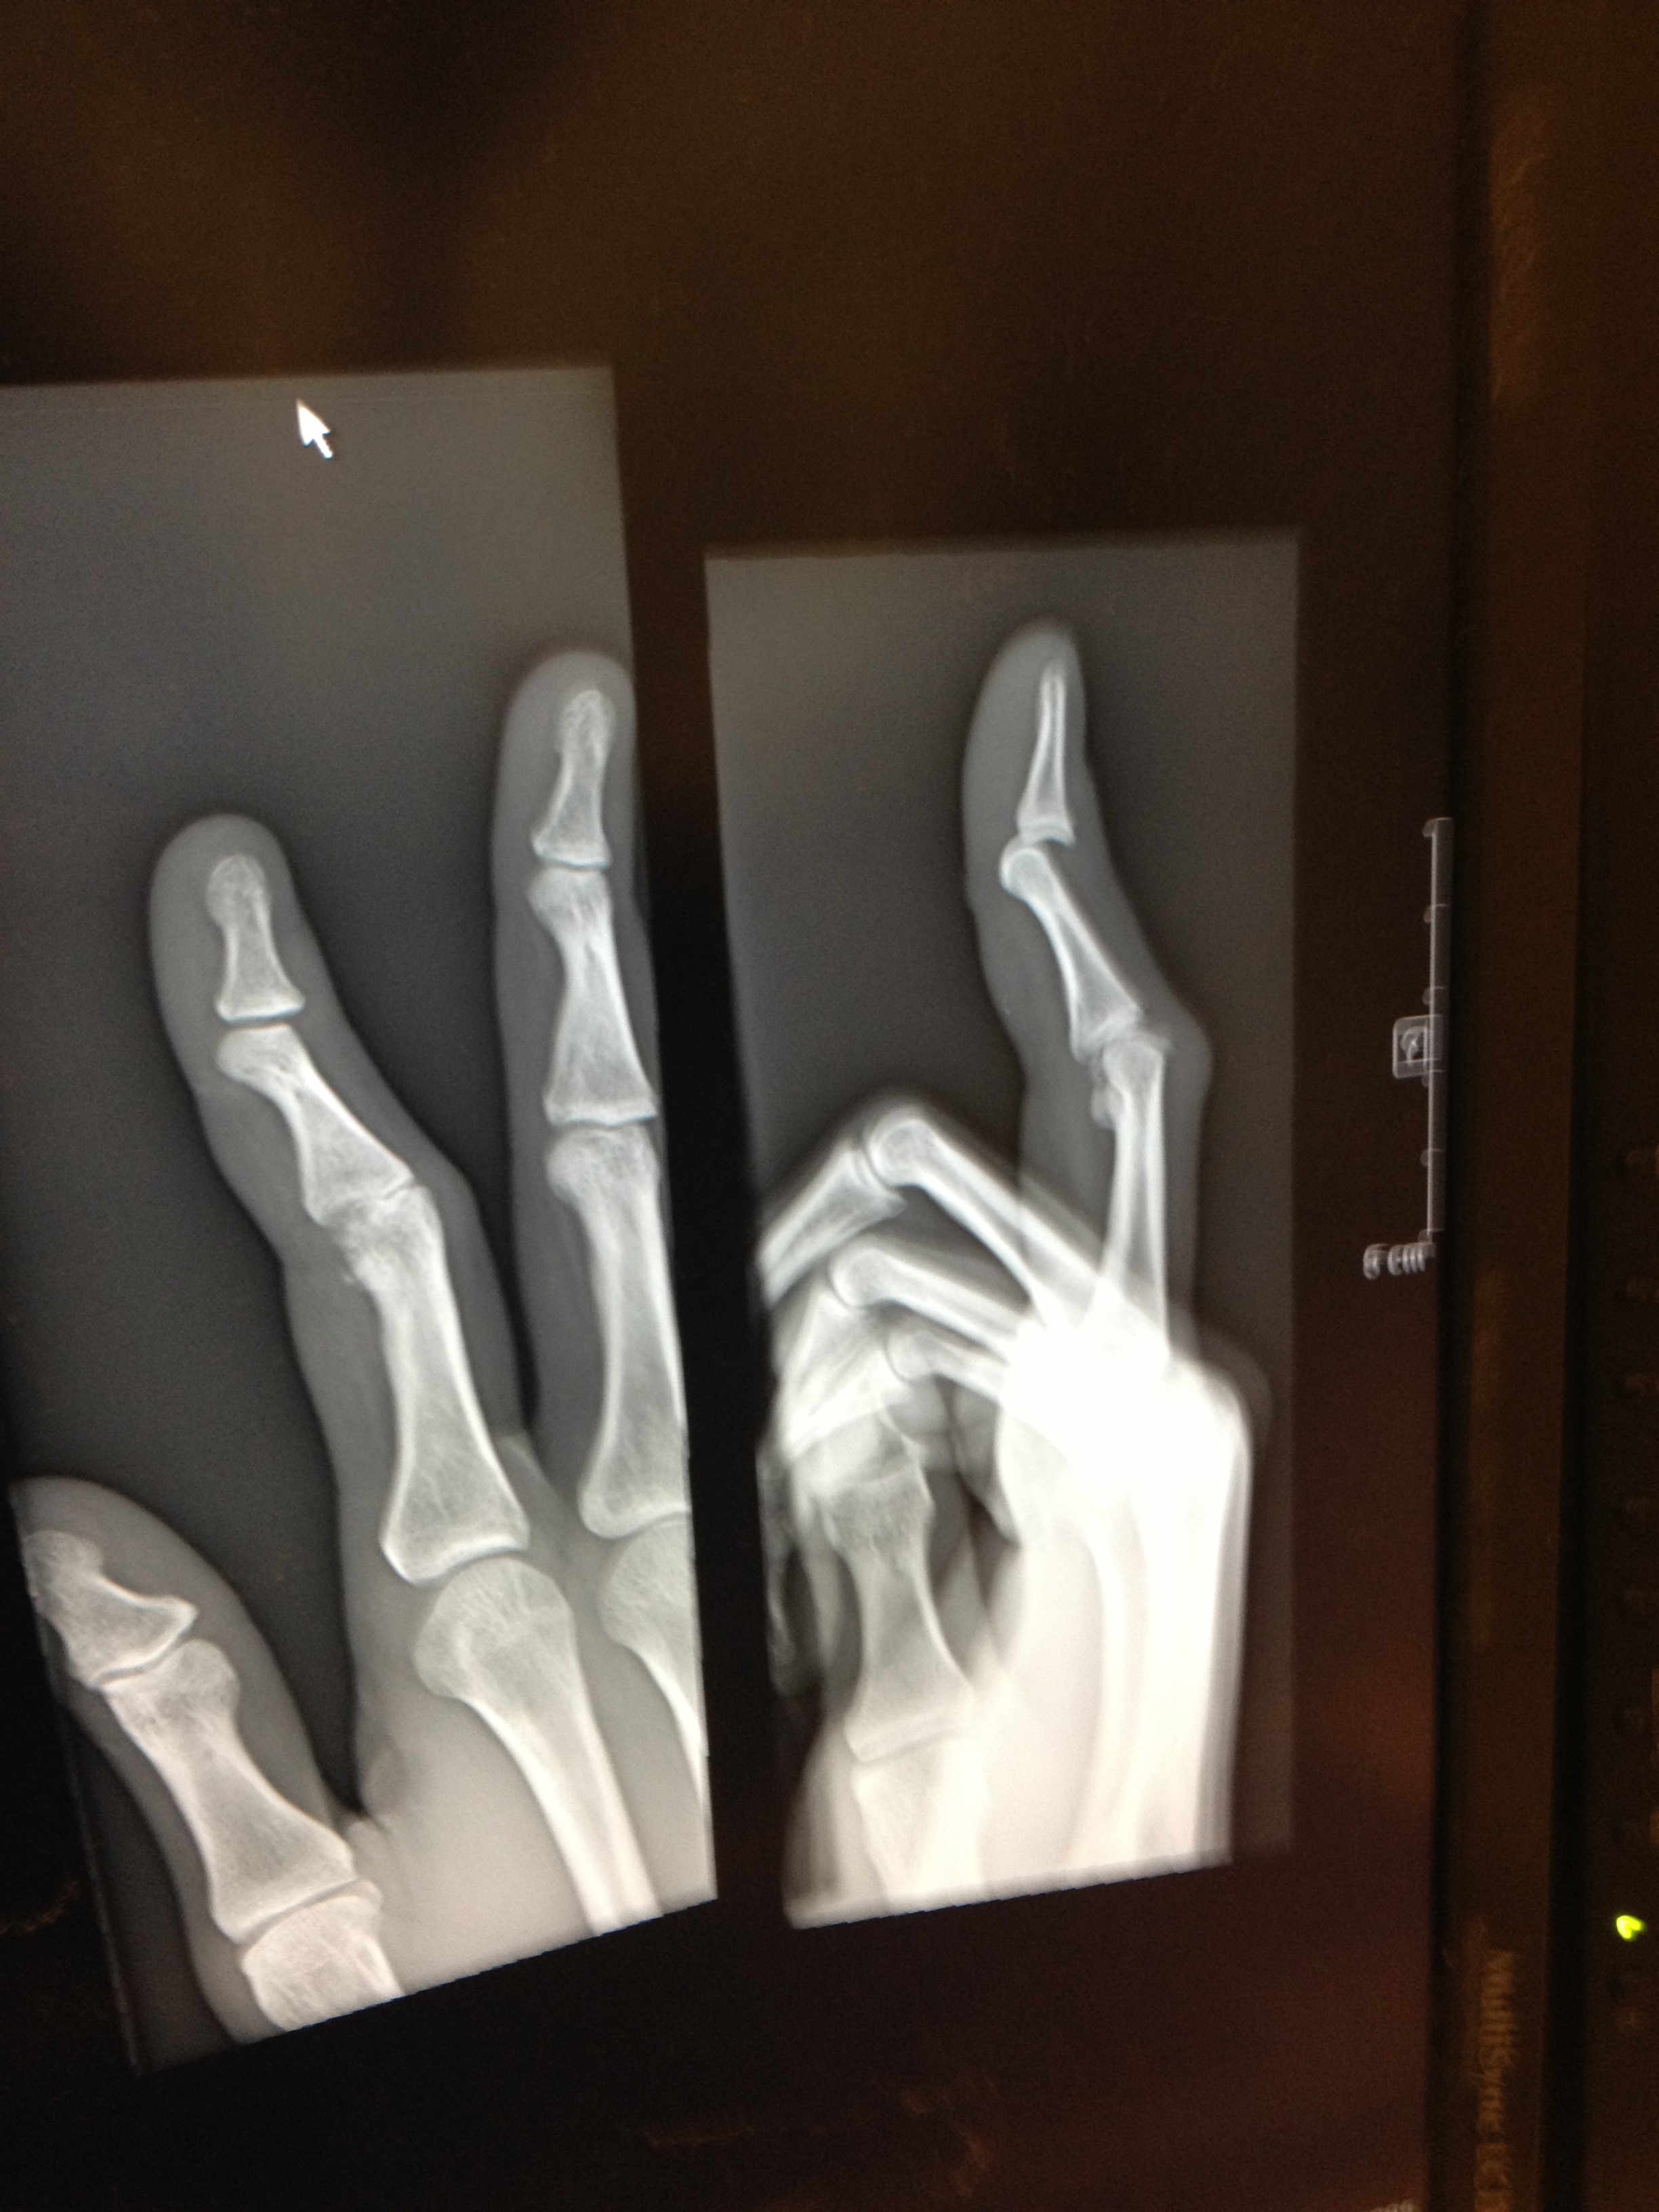

I think the long term outlook is that the move will be better for my health. Except for two things: One, public transportation here is a joke, so I now drive pretty much daily. I don’t have an actuarial table handy but that can’t increase life expectancy. And, two, I broke my right, index finger playing softball in mid-May. (That’s an X-ray of the dislocation and fracture above.) The bone and tendon have healed, but I’m still having trouble restoring the full range of motion to my finger. In my nine years of living in New York, I don’t think I ever saw the inside of an emergency room. I was in one within two months of moving here.